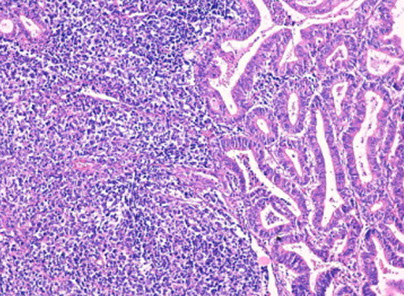

MMMT

Carcinosarcoma

Malignant mixed mullerian tumor (MMMT, carcinosarcoma)

Rare, biphasic high grade tumor with epithelium and stroma which can occur anywhere in female rep tract

Micro: biphasic, c carcinoma and sarcomatous parts

Epithelial portion can be em, serous, clear cell, undifferentiated, squamous, while stroma can be homologous / heterologous

Homologous: (native to the tumor site) endometrial stromal sarcoma or leiomyosarcoma or undifferentiated sarcoma

Heterologous: (not native to the tumor site) muscle, cartilage, bone, fat